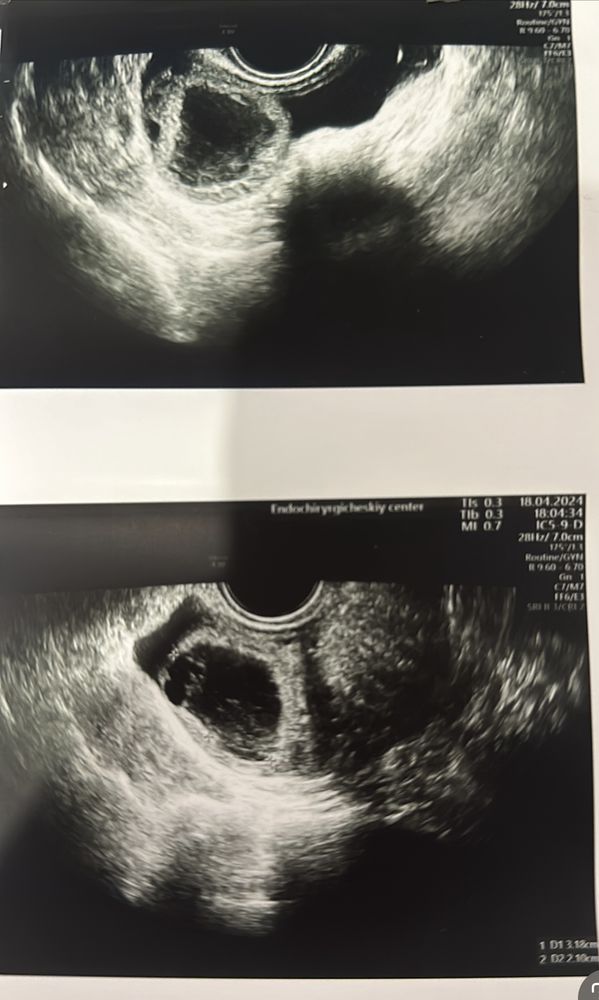

Всем здравствуйте. Подскажите, пожалуйста, а то я начиталась всякого в интернете. К врачу только 27 числа, вот не могу ждать, это правда киста такая? И это опасно? Я делала стимуляцию в том месяце, провальная. Вот врач сказала именно в данную дату сходить на фолликулометрию. А то я читала , что врачи путают кисту то с фолликулом, то с беременностью.

Подскажите это киста или доминантный фолликул или вообще беременность?